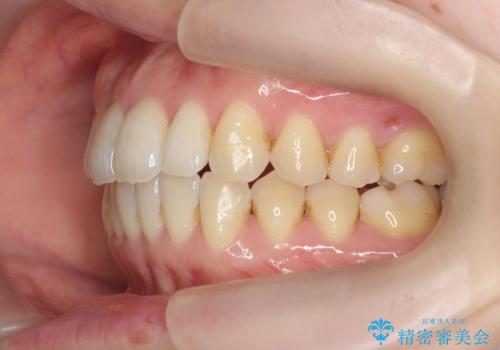

- 出っ歯に見える前歯を治したい、と矯正治療を希望され来院されました。

奥歯の噛み合わせに大きな問題はないので、目立つ前歯の角度・隙間を重点的に整え、審美的な歯並びを獲得できるよう計画します。

治療によりしっかりと前歯の角度が改善され、審美的な歯並びを手に入れることができました。